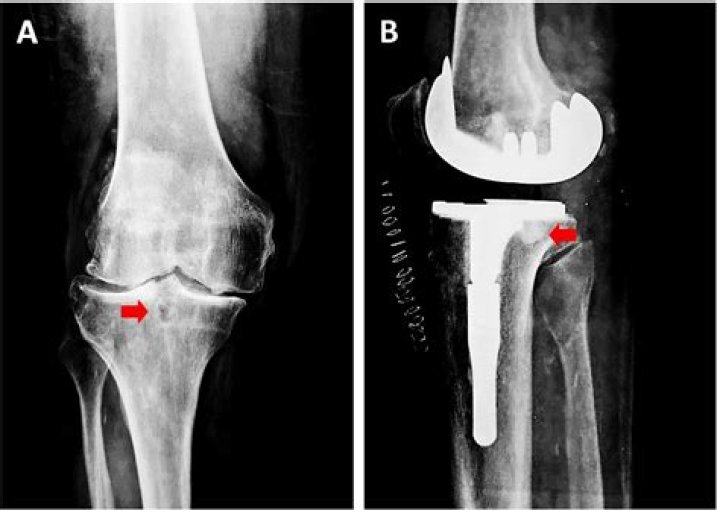

Tibia case daniel photos refers to a collection of images depicting the aftermath of a severe leg injury sustained by a man named Daniel.

The case gained widespread attention due to the graphic nature of the photos and the subsequent legal proceedings that followed. Daniel's injury occurred when he was involved in a motorcycle accident, resulting in a compound fracture of his tibia and fibula.